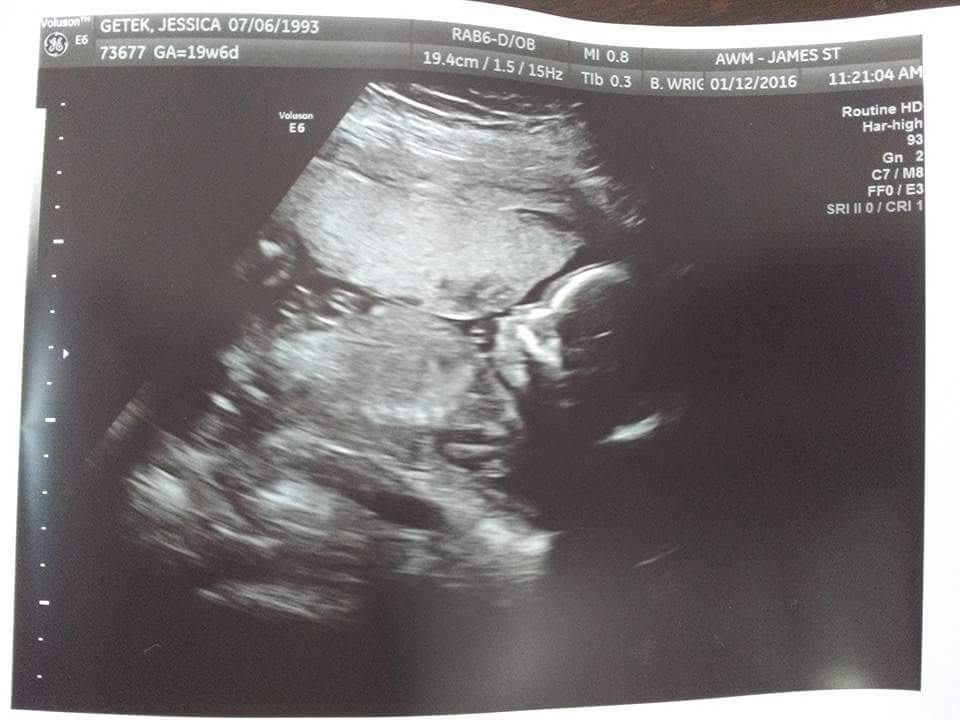

Tuesday morning, January 12, 2016….we all gathered in the exam room…your Mommy, your Daddy, and both of your Grandmas (who had finally just met for the first time!)….quietly watching as pictures were taken of your little head, your little face, your arms and your legs, and your heartbeat. We got to hear that little heart once again, beating even stronger than just a few months before.

You had your tiny legs crossed and tucked up so tightly against your tummy, they couldn’t tell if you were a girl or boy! I think we were all secretly worried that we wouldn’t find out that day! But the technician didn’t give up…and eventually she announced ‘You have a baby girl!’